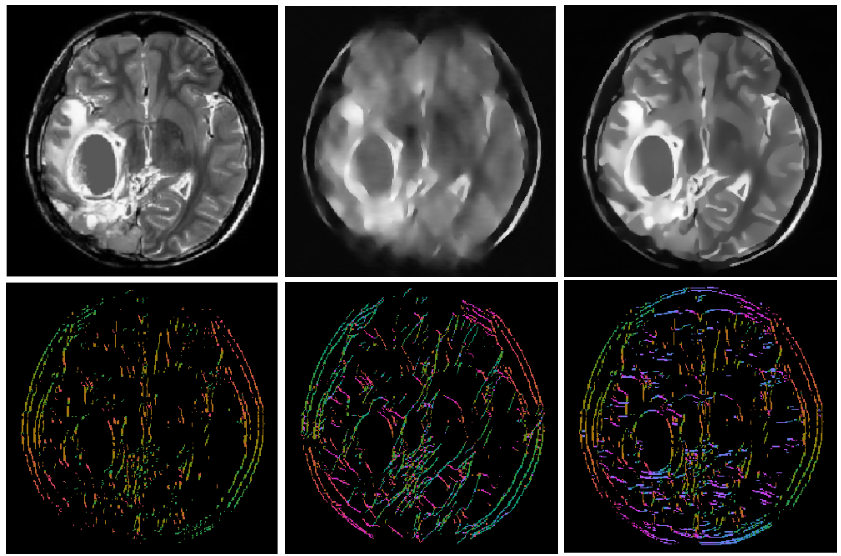

More recently, Andrade-Loarca et al. [AKOP] proposed a method that uses the optimal image representation provided by shearlets and the highly specialized and accurate classification capabilities given by deep neural networks to construct a digital wavefront set extractor named DeNSE (Deep Network Shearlet Edge Extractor). This method outperforms the previous existing methods and poses the capabilities to detect singularities with different degrees of regularity.

On the other hand, one can generalize the concept of edge detection and classification, to other classes, different from the orientations of the edges, this task is known as Semantic Edge Detection (SED). One can perform also high quality semantic edge detection by using existing deep learning approaches, but modifying the input to the shearlet coefficients, and reducing the buffer layers. The shearlet coefficients will perform the heavy lifting necessary so the removed buffer will not affect the performance. In fact Andrade-Loarca et al. [AKO] showed that this reduce the number of learnable parameters and augments the accuracy.